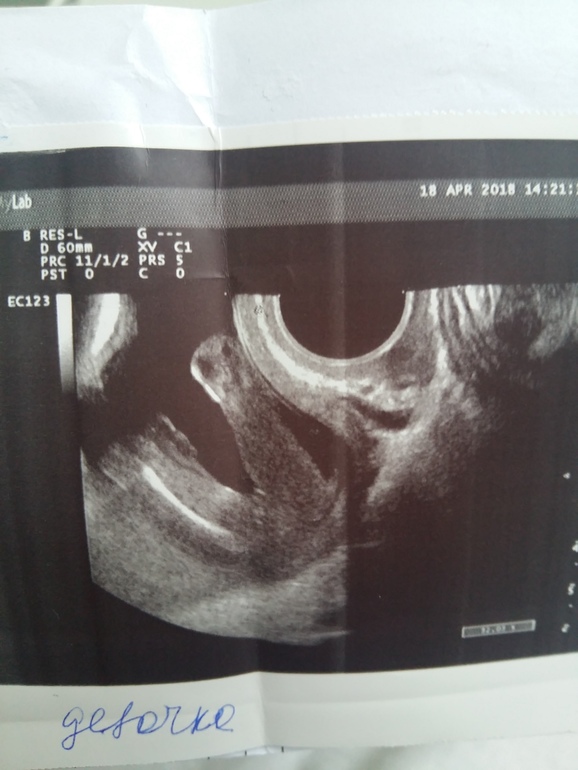

На фото узи ничего не понять, где там вообще ребенок.

Ой,какое чудо чудесное!!! Впервые так явно вижу девочку на фото УЗИ !!!!!! Здесь же нет сомнений ,ПОЗДРАВЛЯЮ!!!!!

На 16 неделе писюн сына с такого же ракурса выглядел сосисочкой, а не пирожком )) сомнений нет - девуля у вас ))